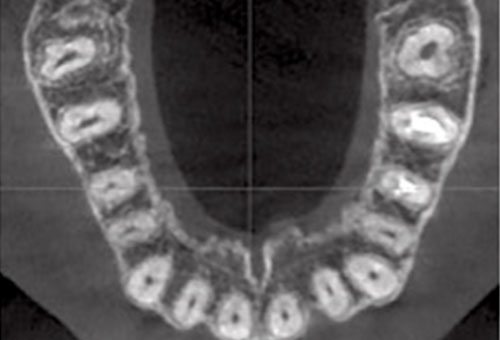

Pre operative CBCT

CBCT axial image showing single rooted tooth 26